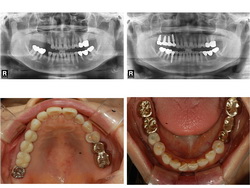

| ¿ÞÂÊ ¾î±Ý´Ï À§¾Æ·¡... |

| 2Â÷ ¼ö¼ú ÈÄ ÀÕ¸öÀÌ ¾Æ¹°¸é º¸Ã¶¹°À» Á¦ÀÛÇÏ°Ô µË´Ï´Ù. ¿©±â¼ ºÎÅÍ´Â ÀÏ¹Ý º¸Ã¶¹° Á¦ÀÛ°ú µ¿ÀÏÇÏ¸ç µû¶ó¼ ±Ý´Ïµµ °¡´ÉÇϰí Ä¡¾Æ»öÀÌ ³ª´Â º¸Ã¶¹°µµ ¸ðµÎ °¡´ÉÇÕ´Ï´Ù. º¸Ã¶¹°Àº ´ëºÎºÐ °íÁ¤µÇ´Â º¸Ã¶¹°À» Á¦ÀÛÇϳª, Ä¡¾Æ°¡ Çϳªµµ ¾ø´Â °æ¿ì¿¡ ÀÖ¾î¼ ÀÓÇöõÆ® °³¼ö¿¡ µû¶ó¼ Ʋ´Ï Çü½ÄÀ¸·Î Á¦ÀÛÇÏ´Â °æ¿ìµµ ÀÖ½À´Ï´Ù. Ʋ´Ï Çü½ÄÀ¸·Î Á¦ÀÛÇÏ°Ô µÇ´õ¶óµµ ¾Ã´Â Èû°ú À¯Áö·ÂÀº ÀÏ¹Ý Æ²´Ïº¸´Ù ¿ì¼öÇÕ´Ï´Ù. |

| Àΰø »Ñ¸®¸¦ ½É´Â ¼ö¼úÀÔ´Ï´Ù. »À¿¡ Àû´ç·®ÀÇ ±¸¸ÛÀ» ¶Õ°í Àΰø »Ñ¸®¸¦ ½É¾îµÎ°Ô µË´Ï´Ù. Ä¡¾Æ ÁÖÀ§¿¡ ¿°ÁõÀÌ ½ÉÇÏÁö ¾ÊÀ¸¸é Ä¡¾Æ¸¦ »Ì°í ´çÀÏ¿¡ ¹Ù·Î ÀÓÇöõÆ®¸¦ ½Ä¸³ÇÏ´Â °æ¿ìµµ ÀÖ½À´Ï´Ù. ÀÌÈÄ ¾Æ·¡ Åο¡¼´Â 2-3°³¿ù, ÀÅο¡¼´Â 4-6°³¿ùÀÇ Ä¡À¯±â°£ÀÌ ÇÊ¿äÇÏ¸ç »ÀÀ̽ÄÀ» Çß´Ù¸é Á» ´õ ¿À·£ ±â°£µ¿¾È ±â´Ù·Á¾ß ÇÏ´Â °æ¿ìµµ ÀÖ½À´Ï´Ù. ÀϹÝÀûÀ¸·Î ÀÌ ±â°£ Áß¿¡´Â ÀÓÇöõÆ®°¡ ÈûÀ» ¹ÞÀ¸¸é Ä¡À¯¿¡ ¹æÇذ¡ µÇ±â ¶§¹®¿¡ º¸Ã¶¹°À» Á¦ÀÛÇÏÁö ¾ÊÀº »óÅ¿¡¼ Ä¡À¯¸¦ ½ÃŰÁö¸¸ ¾Õ´Ï¿Í °°ÀÌ ½É¹ÌÀûÀÎ ¹®Á¦°¡ Àְųª ¶Ç´Â ¿©·¯ °³ÀÇ ÀÓÇöõÆ®¸¦ ÀÌ¿ëÇÏ°Ô µÇ´Â °æ¿ì ¹Ù·Î º¸Ã¶¹°À» Á¦ÀÛÇÒ ¼ö ÀÖ´Â °æ¿ìµéµµ ÀÖ½À´Ï´Ù. |